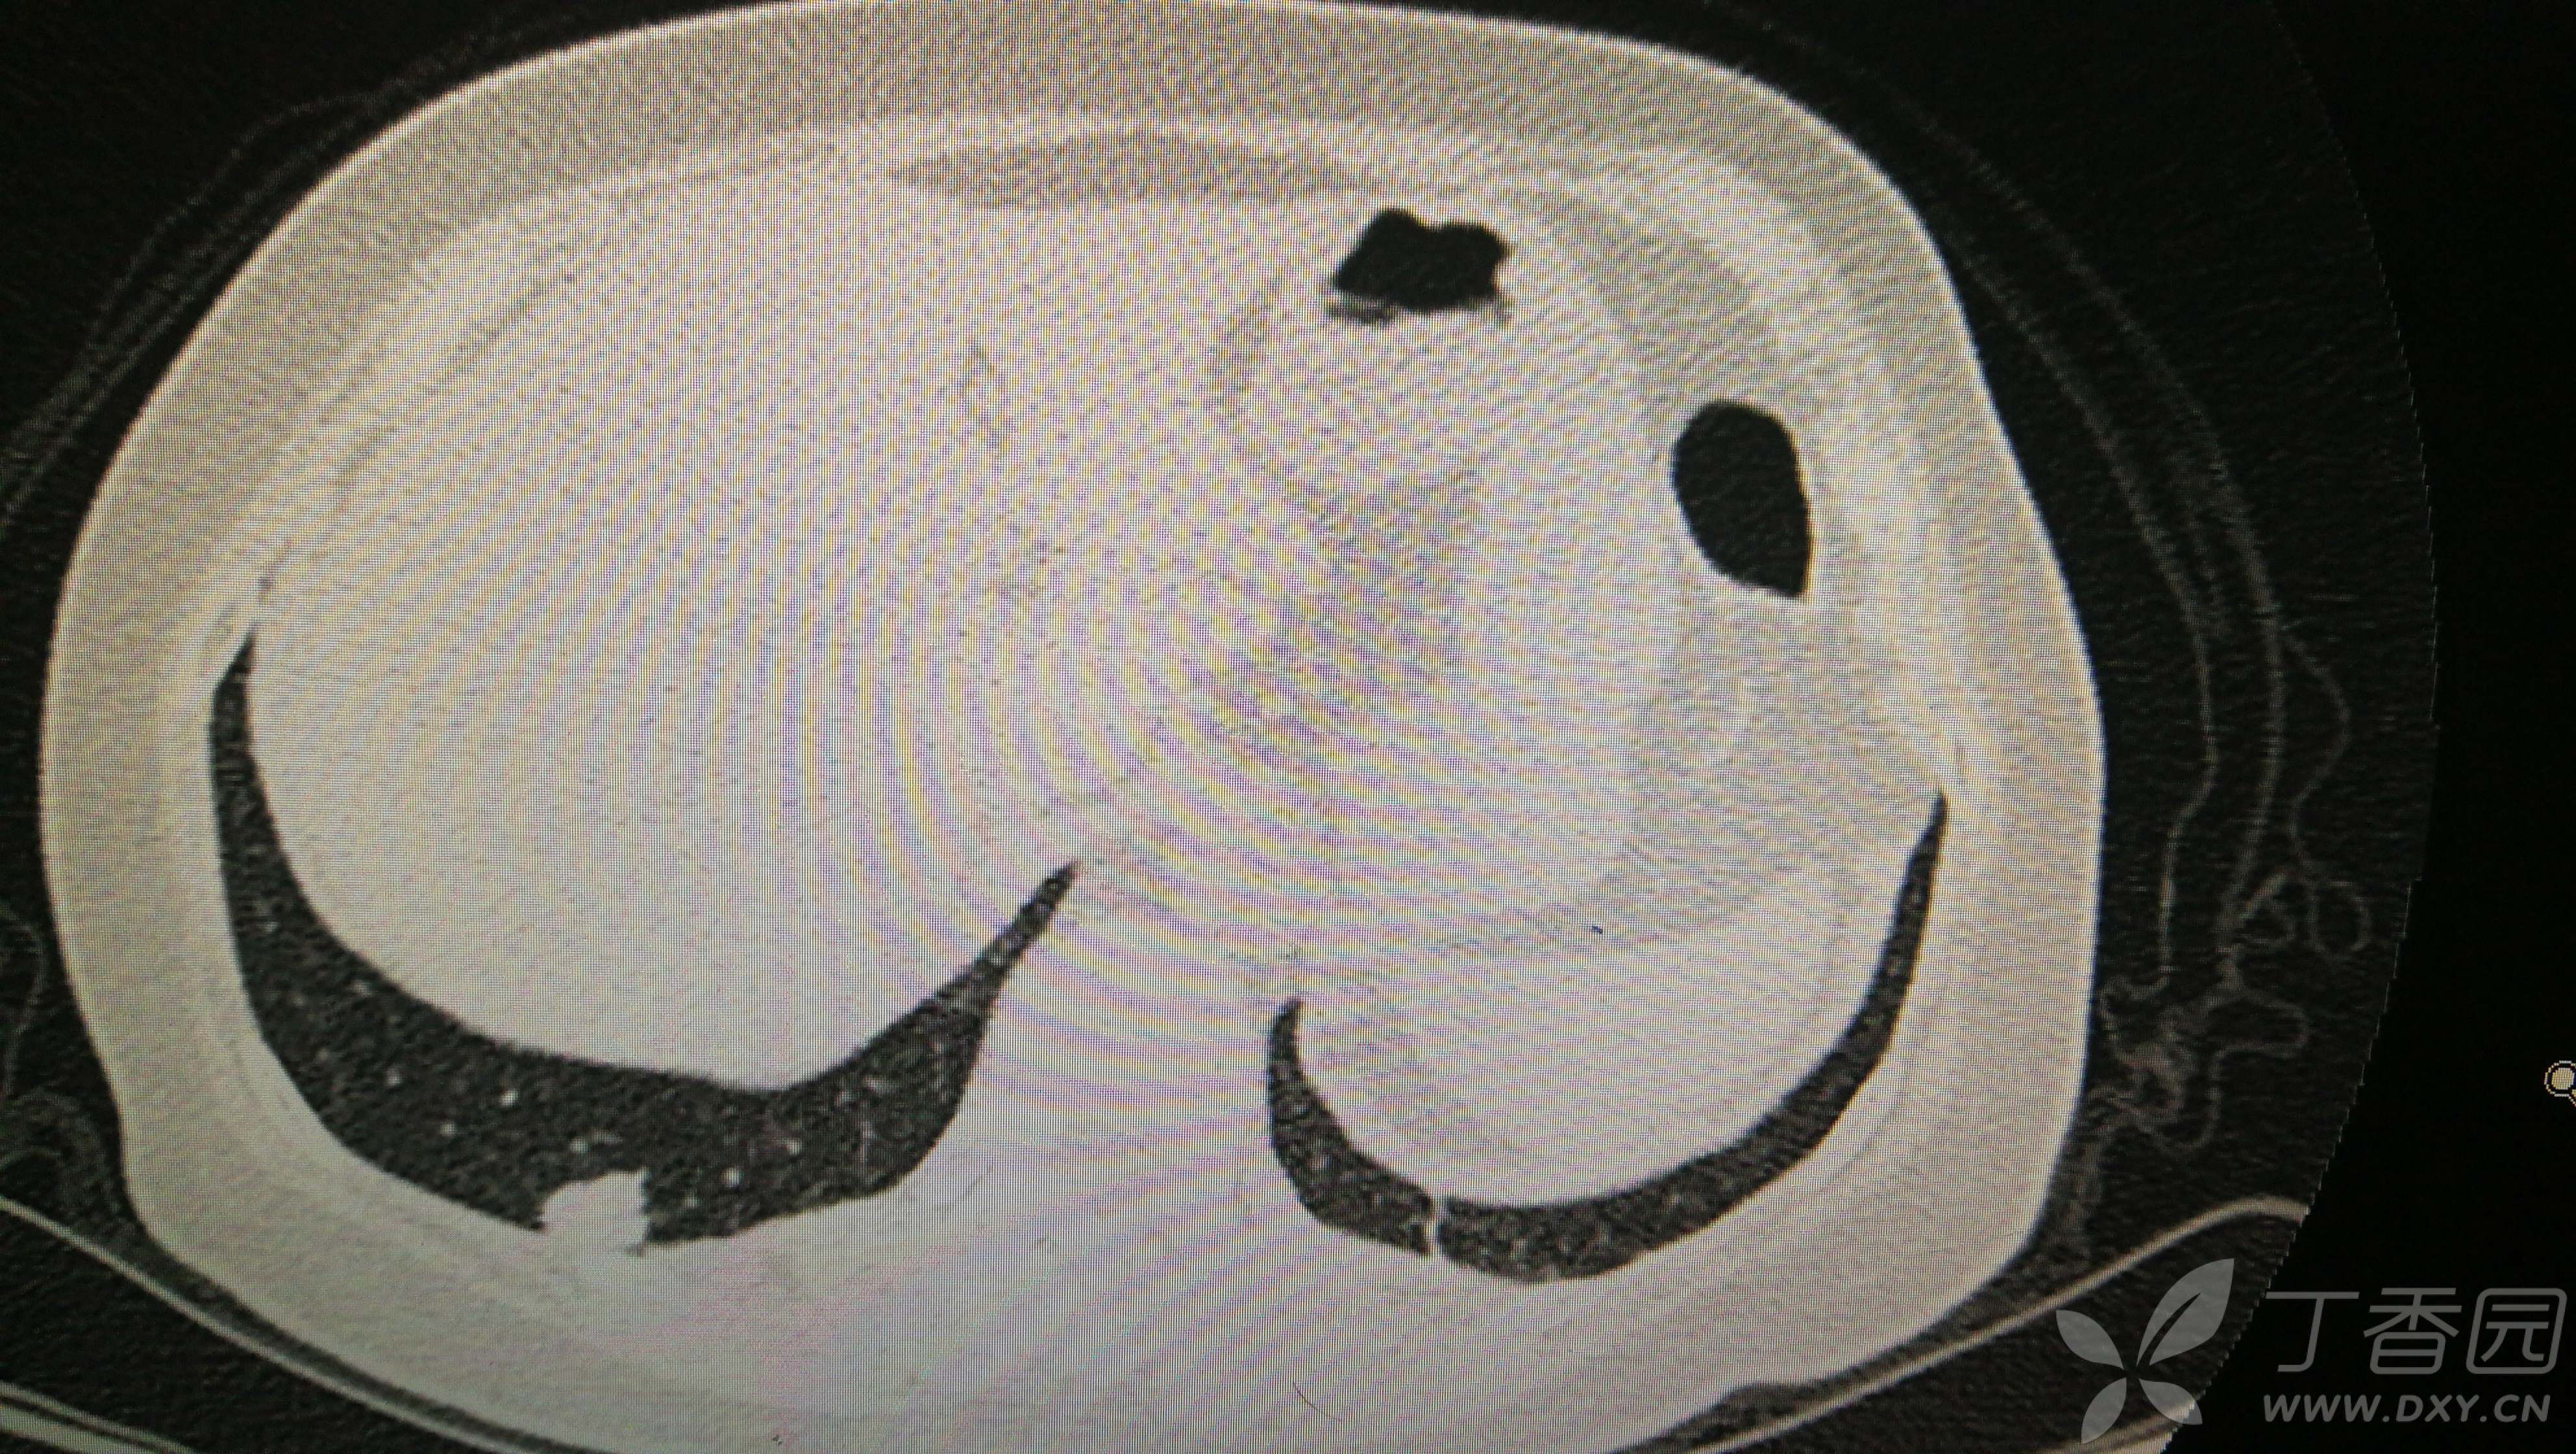

由于患者高龄,合并内科疾病,且肺部结节多发,其他部位检查未见明显肿瘤病灶。因此,手术行胸腔镜右下肺外后基底段切除+右上肺楔形切除术。